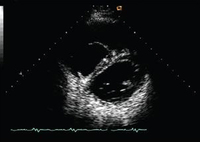

Visualização ecocardiográfica em eixo curto em um paciente com regurgitação pulmonar após reparo de tetralogia de Fallot. O paciente tem ventrículo direito restritivo e a visualização ecocardiográfica em eixo curto revela ventrículo direito pequeno

De: Chaturvedi RR, Redington AN. Heart. 2007 Jul;93(7):880-9; usado com permissão